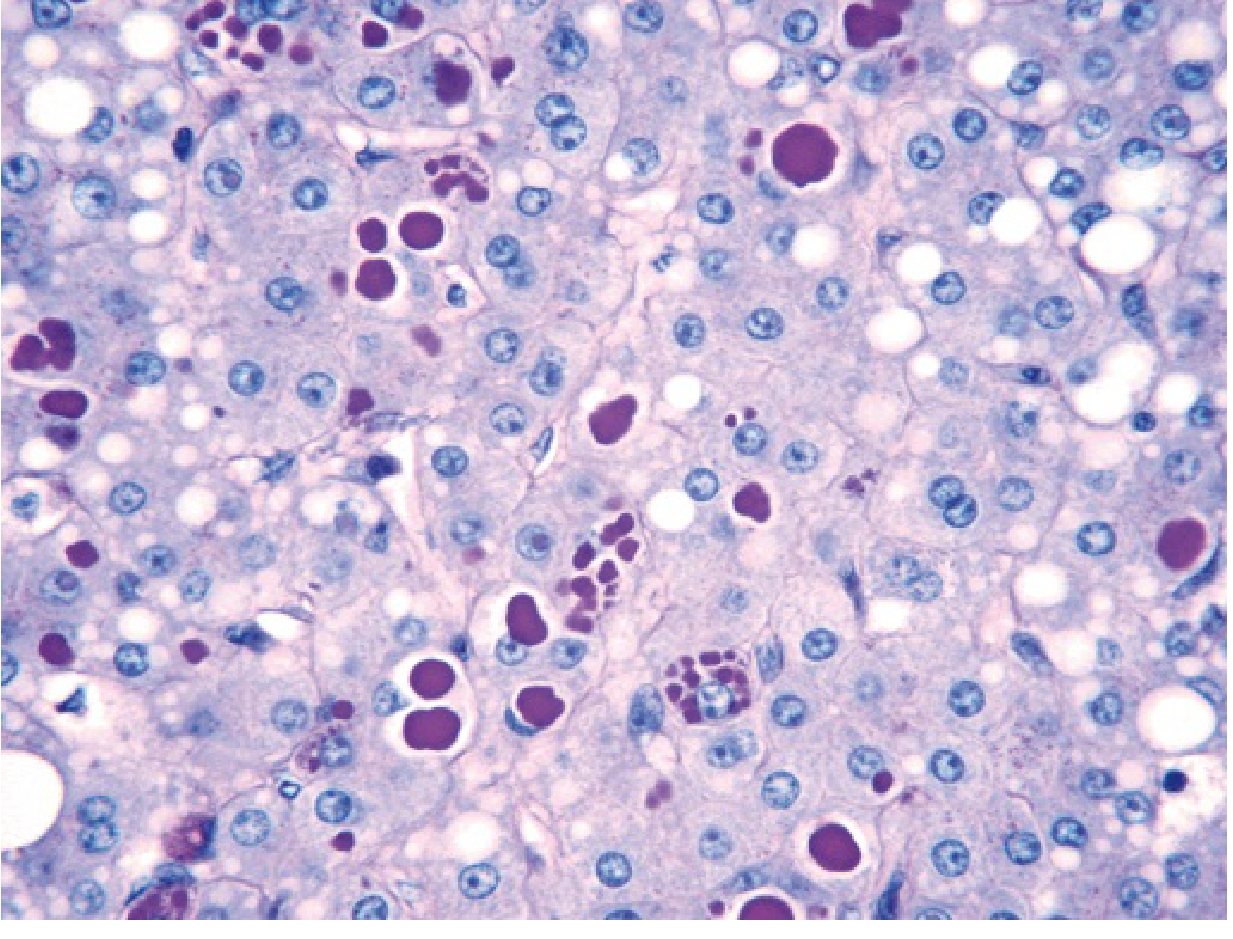

Histology (High-Yield)

• Liver biopsy: Round-to-oval cytoplasmic globular inclusions in hepatocytes

• Stain: PAS-positive, diastase-resistant (magenta globules)

• Periportal hepatocytes affected first

PAS stain showing magenta cytoplasmic globules in hepatocytes

α1AT deficiency: PAS stain after diastase digestion showing characteristic magenta cytoplasmic globules in hepatocytes.